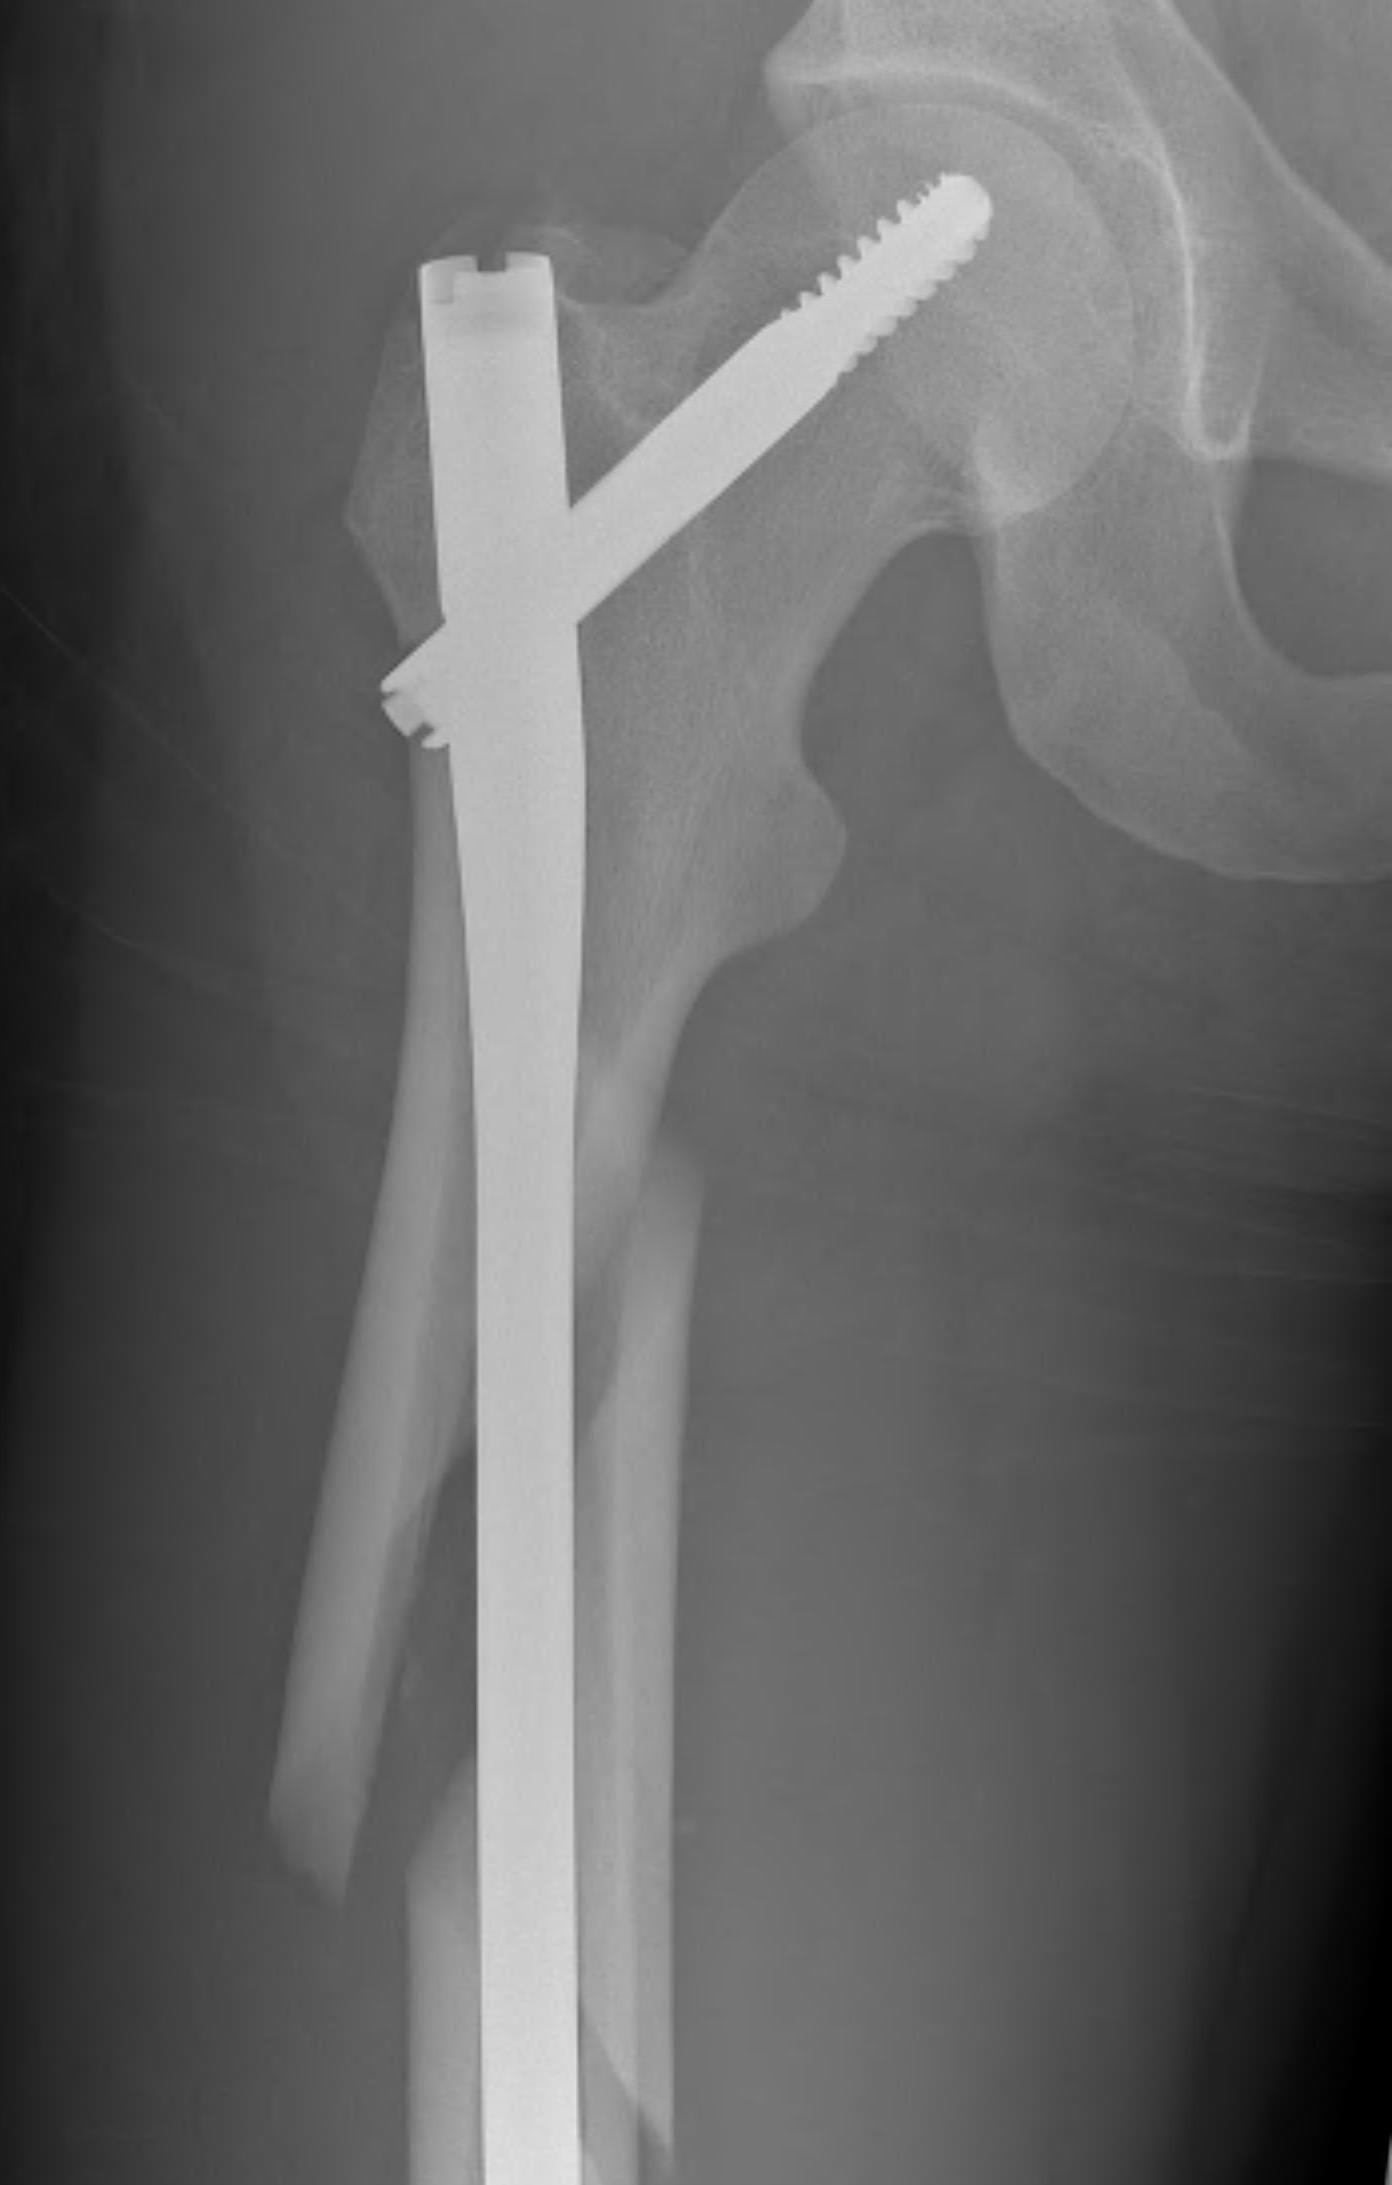

1. Proximal fragment flexed, in varus and externally rotated with distal fragment adducted

- iliopsoas flexes proximal fragment

- abductors cause varus of proximal fragment

- external rotators rotate proximal fragment

- adductors medialize distal fragment

3. Varus malreduction associated with non union

- anatomical reduction key to union

- case series of 102 subtrochanteric fractures treated with IMN

- all nonunion occurred with varus > 10 degrees

Position

Lateral

- helps reduction of distal fragment to flexed proximal fragment

- easier piriformis access

Supine on traction table

- easier imaging

- longitudinal traction